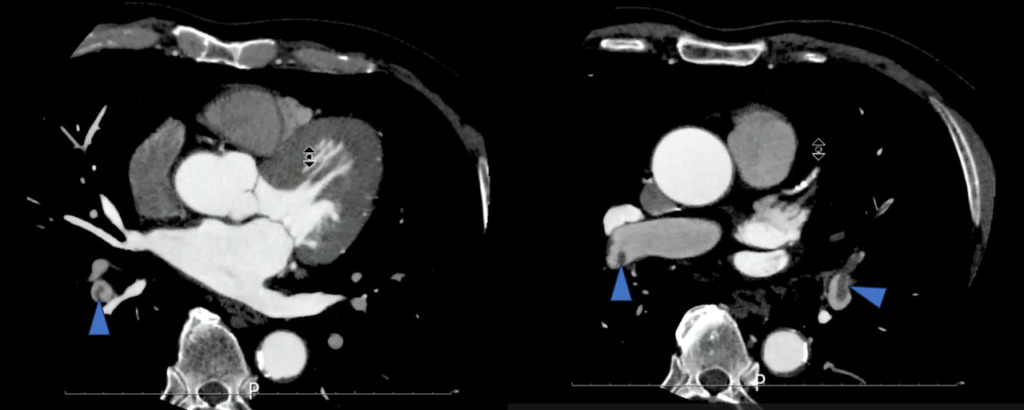

上行動脈にROIを置いたボーラストラッキングにてイオパミロン370 造影剤注入速度5.0ml/sec 造影剤量65mlにて撮影された画像です。

両側の肺動脈に造影不良域(filling defect)を認めます。

肺動脈塞栓(PTE)を疑う画像です。

この症例では撮影者がリアルタイムにこの所見に気づき、すぐ放射線科医に報告し肺動脈と深部静脈を観察するために胸腹部の追加撮影を行いました。

(当院では造影CTを行う際に放射線科医も同席するためその場で確認することができ、撮影を追加しました。本来であれば残った造影剤を全部注入し肺動脈の検査と深部静脈の検査を行う方が良かったのですが、腎機能も低かったのでこのまま撮影することとなりました。その際、少しでも造影効果を高めるために管電圧を80~100kVに下げて撮影を行いました)

その時の画像がこちらです。

造影後3分で追加撮影をしました。

この方は検査前情報にはなかったのですが、右のTKA術後の方でした。右膝関節術部周囲を主体に下腿~大腿骨遠位レベルにfilling defectが複数認められました。

管電圧を下げて撮影することで、造影剤が60mlほどでも深部静脈の評価が可能でした。時間経過で造影効果が低くなった肺動脈の観察も観察することができました。

現場で症例に気づき、寝台から降ろさずに放射線科に相談し腎機能低下していることから追加造影は行わずに管電圧を低くして撮影に対応し、病変部が観察できた症例になります。